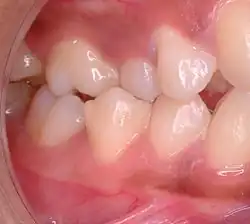

Malocclusion in 10-year-old girl | |